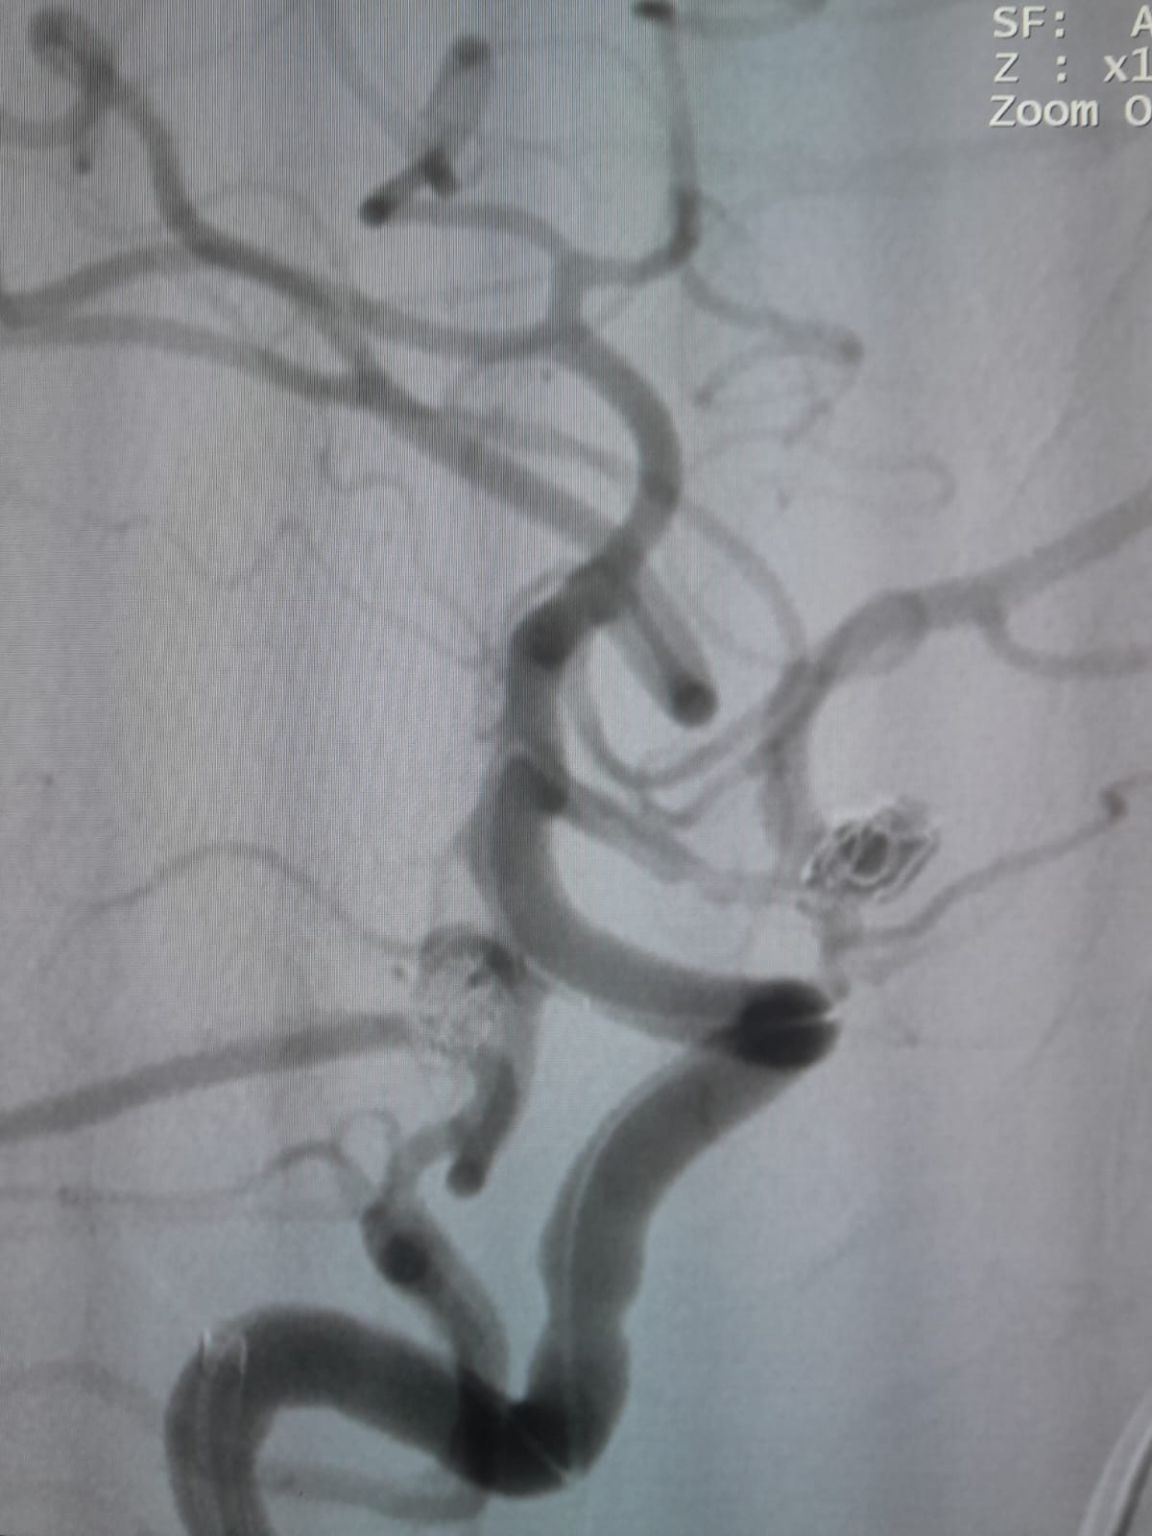

The patient was diagnosed with a newly discovered anterior communicating artery (AComA) saccular aneurysm and a posterior communicating artery (PComA) aneurysm that had been previously treated with coil embolization. Follow-up imaging revealed residual filling in the PComA aneurysm, requiring additional intervention.

Posterior Communicating Artery Aneurysm (Re-treatment)

During follow-up, residual filling was noted in the previously treated posterior communicating artery aneurysm. The team re-accessed the site using Frepass® Disposable Microcatheter (TJMC18 Plus) and successfully deployed a Nuva® Flow Diverter (TJED-D-4.5-16), which demonstrated ideal wall apposition and excellent flow diversion, leading to highly satisfactory treatment outcomes.